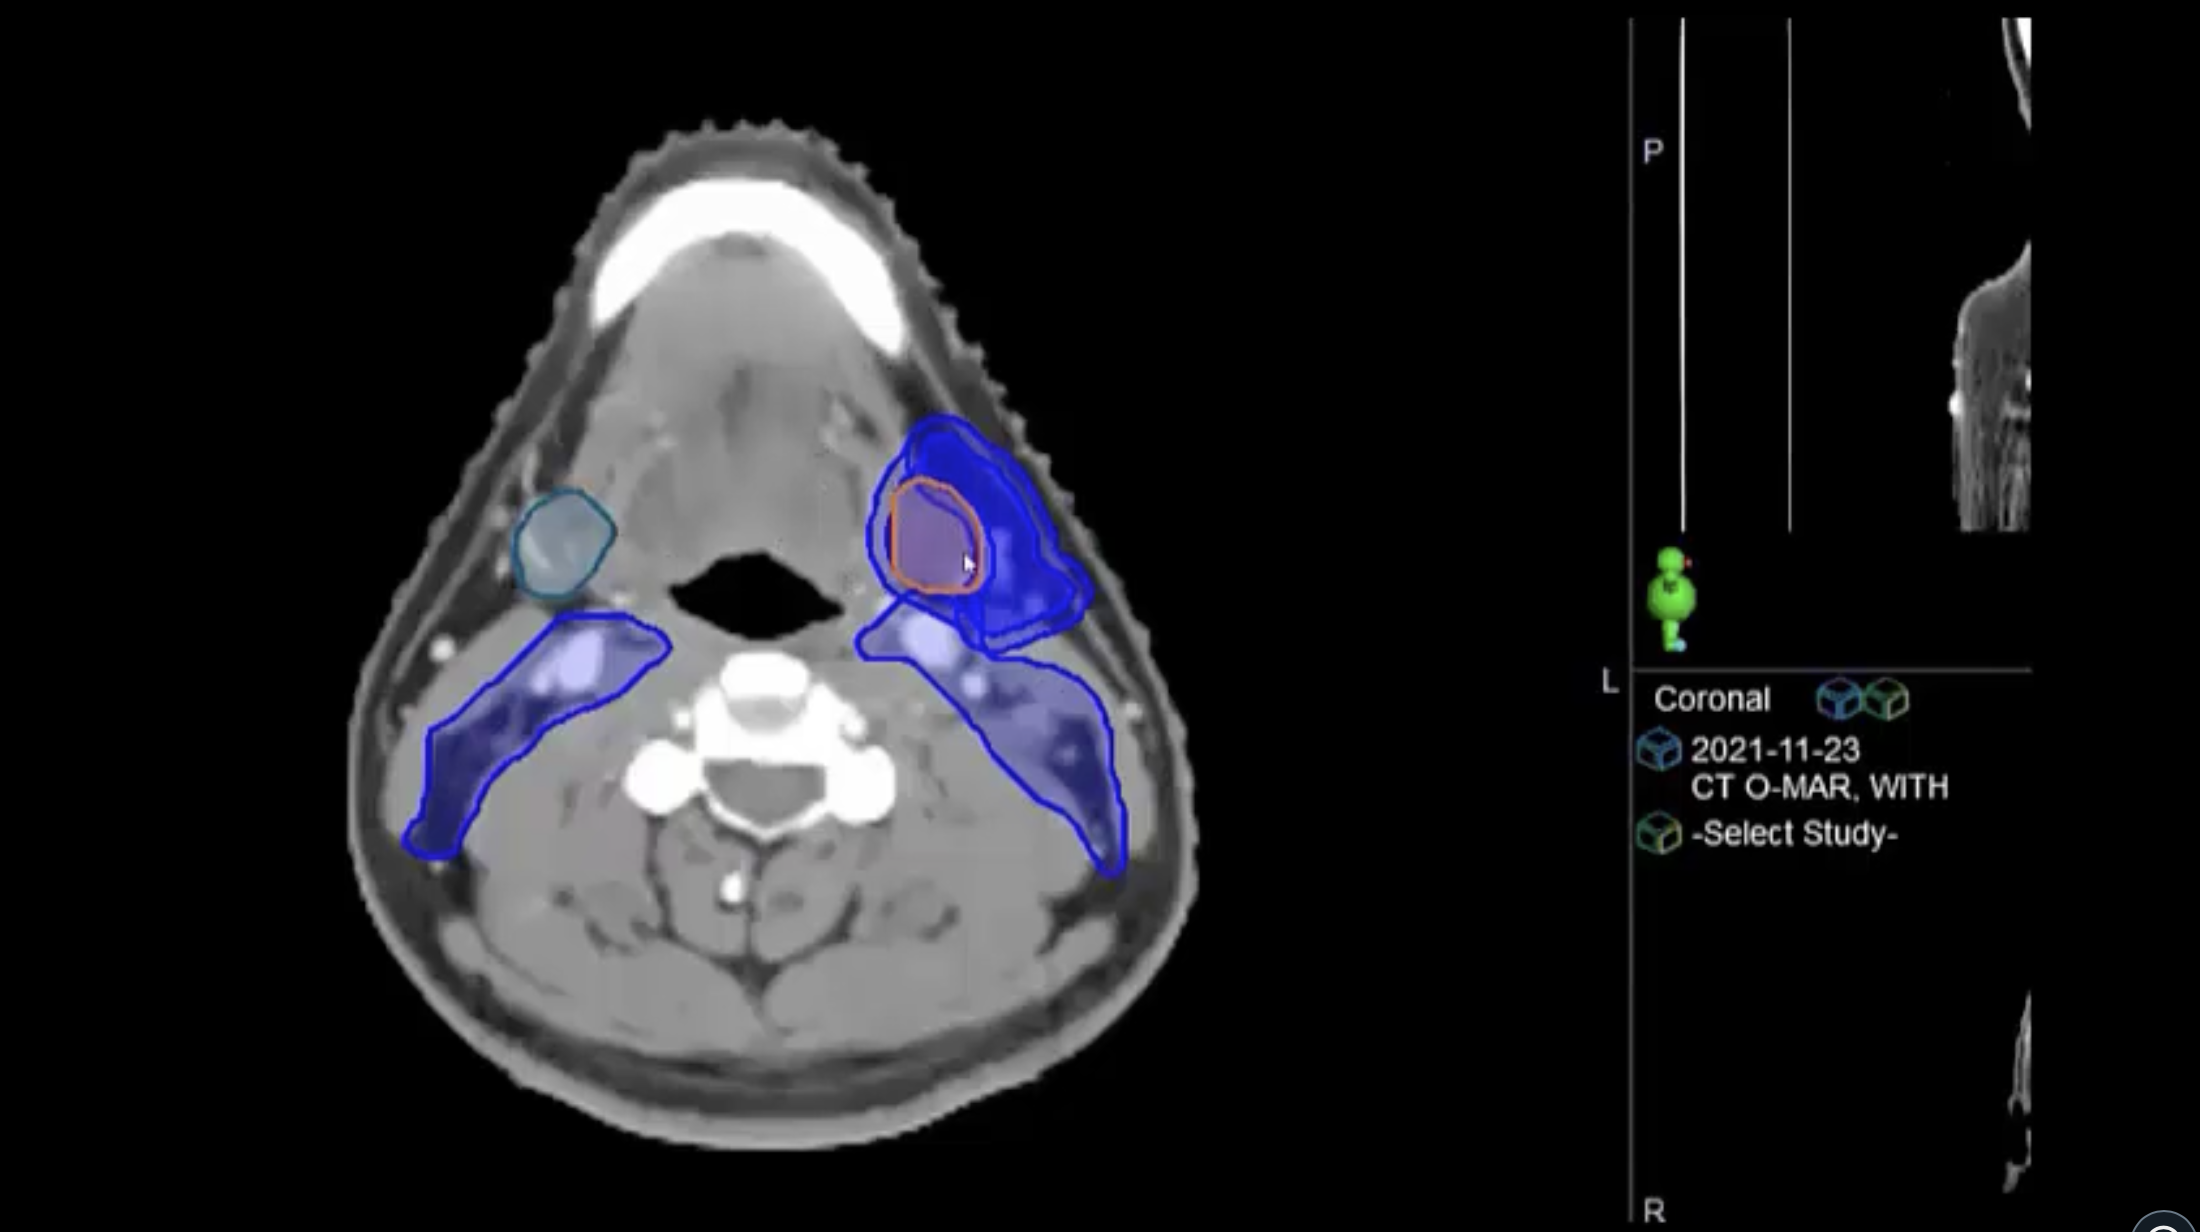

11/29/2021 - Dr. David Sher - Radiation Oncology - US Head & Neck

unknown primary